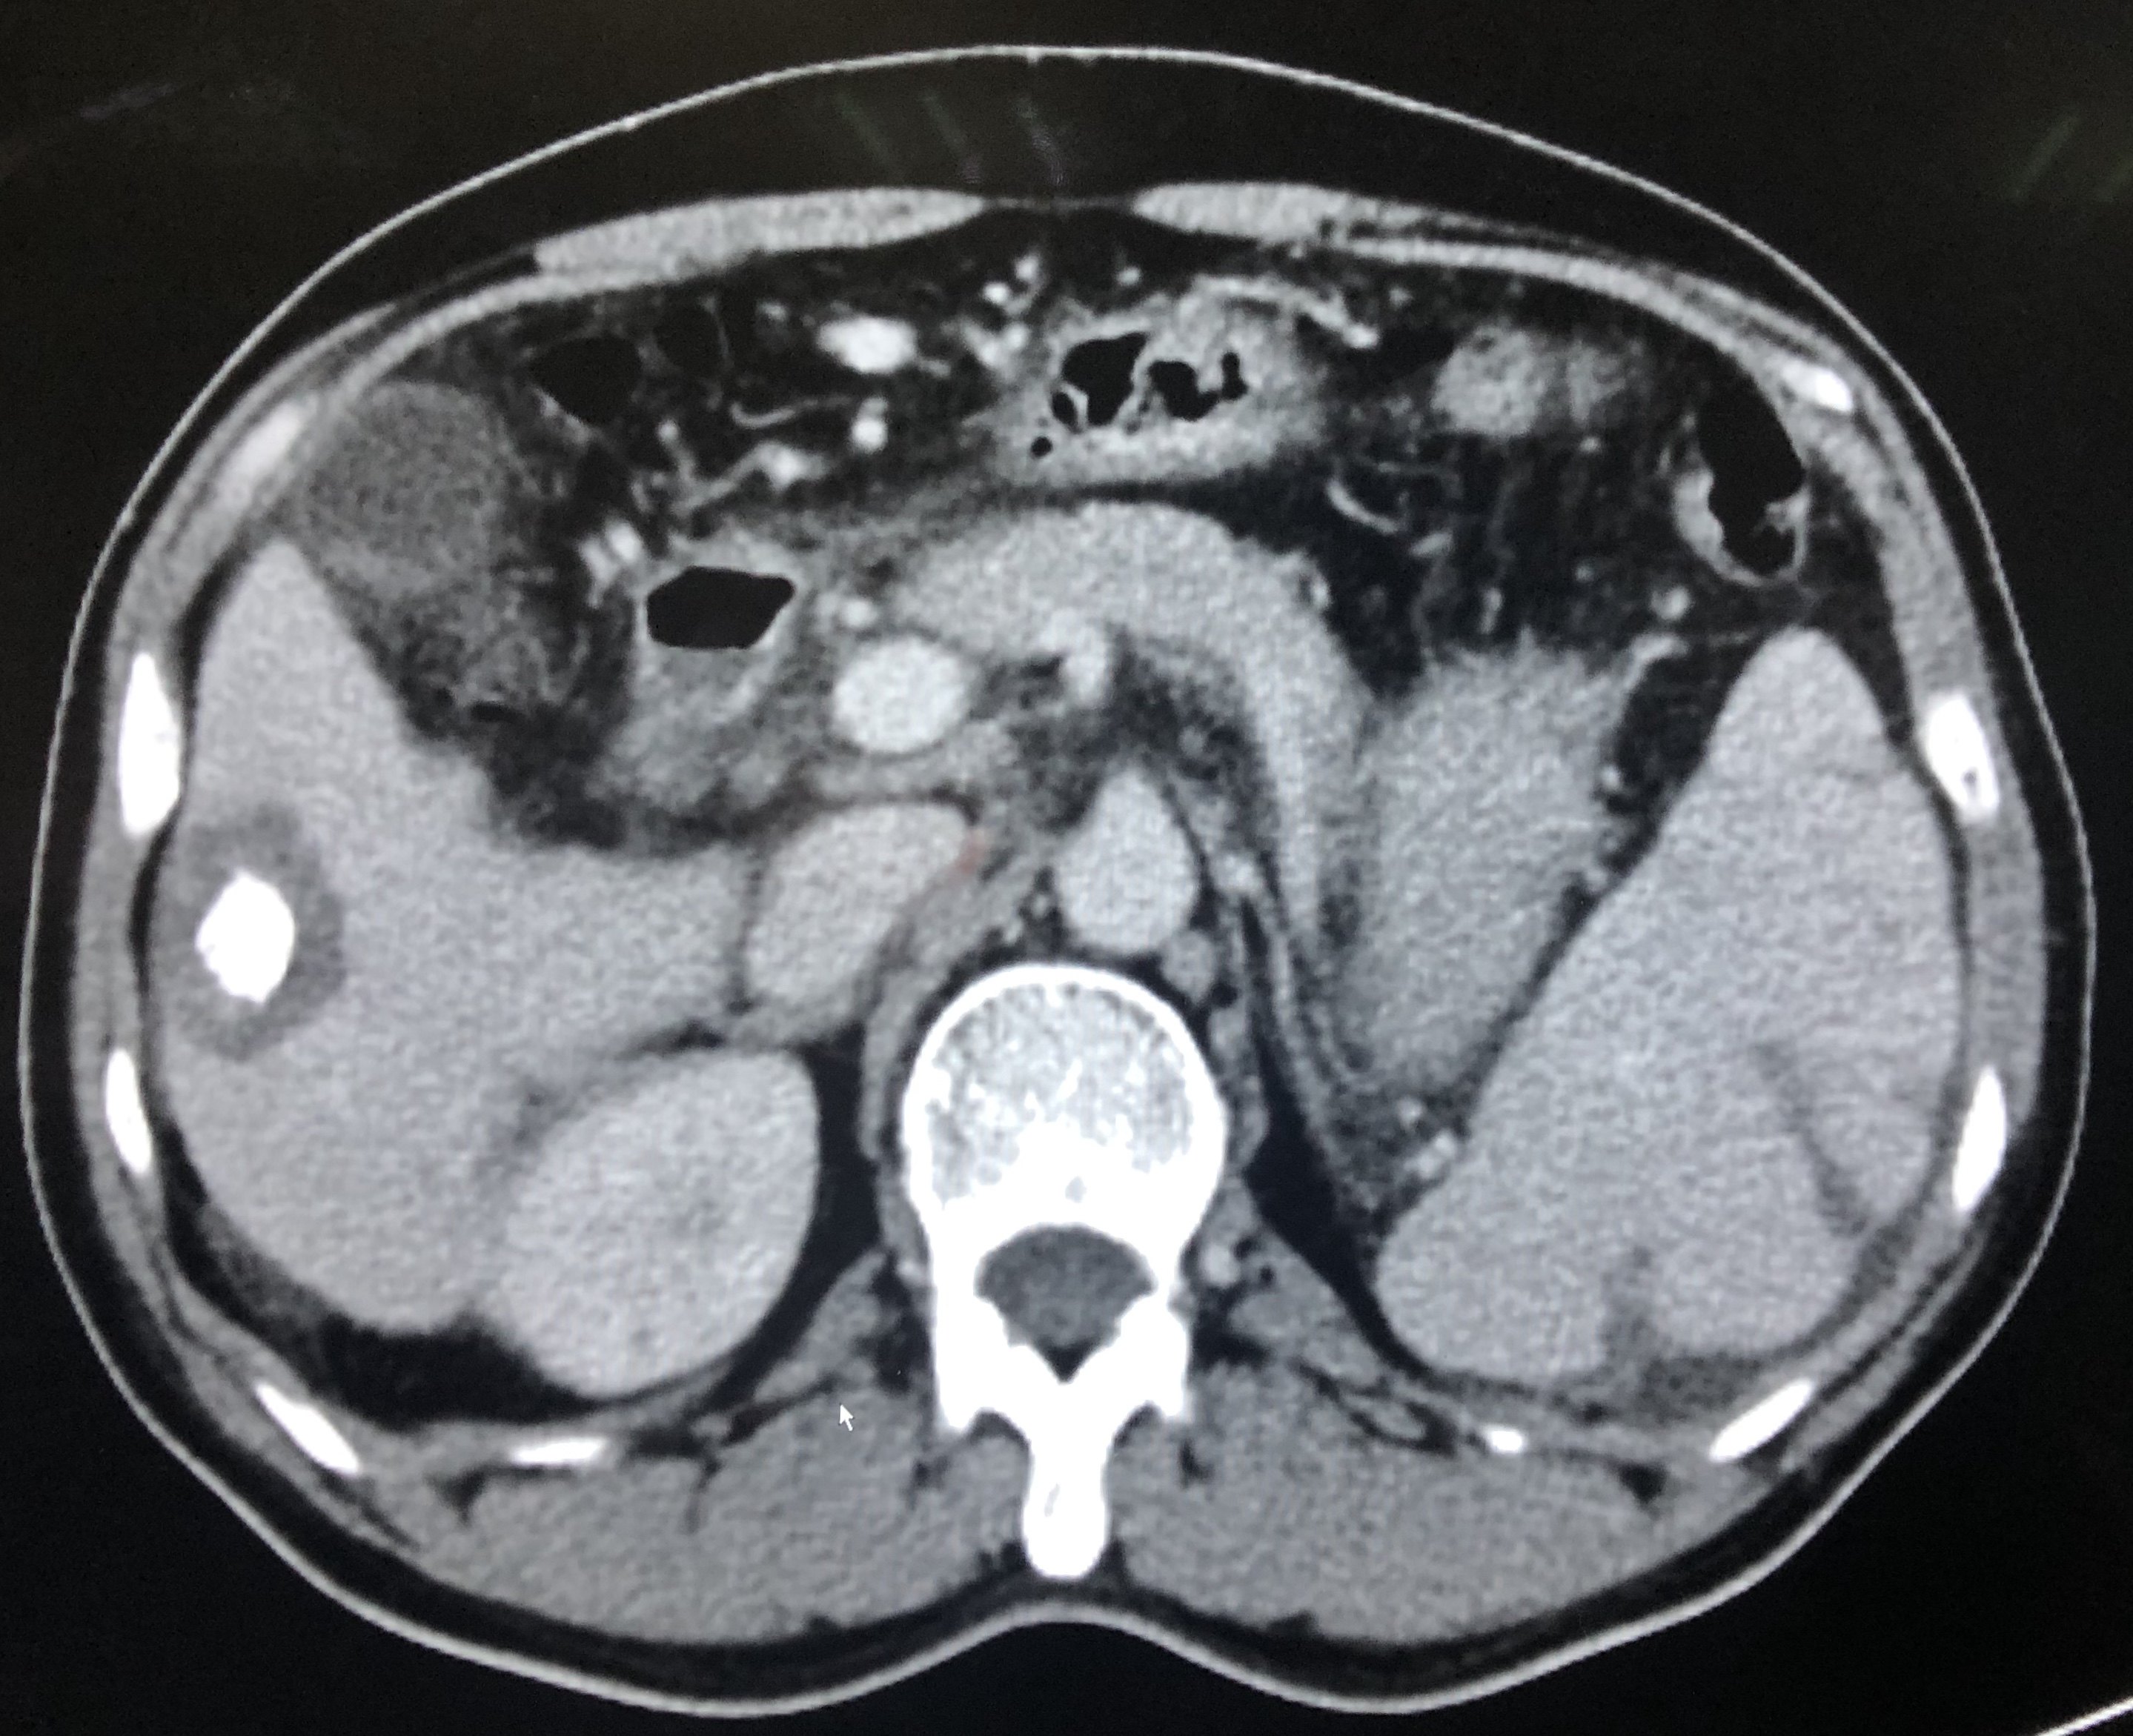

患者男性53岁,多年乙肝肝硬化门脉高压脾功能亢进病史,2018年发现右肝小肝癌。血小板35*10^9/L,行经肝动脉化疗栓塞术加脾动脉主干栓塞术,后续序贯肝癌微波消融及脾消融,随诊一年余肝癌完全灭活,无复发,脾亢基本纠正,血小板85*10^9/L。

右肝肿瘤门脉期低密度,为肝癌典型表现。